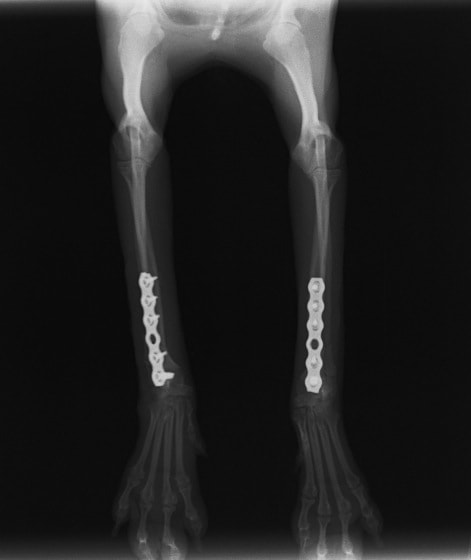

トイプードル 右遠位橈尺骨短斜骨折のALPSによる内固定

Locking Compression Plate

LCPは、スクリュー(ネジ)とプレート(金属の板)をロックする特殊な構造により骨折部位を固定する新しい世代のプレートシステムです。ひとつのホールでロッキングスクリューとスタンダードスクリューの使用を選択できるユニークな構造をしているため、骨折断端間の圧迫を目的とした従来型プレート固定法に加え、高い角度安定性を有するロッキングスクリューを用いた固定法の選択が可能です。従来のプレートシステムでは困難だった部分の骨折や癒合不全の症例に高い治療効果をもたらします。